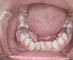

С учетом клинико-морфологических особенностей различают фиброматозный (рис. 1) ангиоматозный (рис. 2) и гигантоклеточный (рис. 3) эпулис. Первые два являются следствием выраженной продуктивной тканевой реакции при хроническом воспалении десны. Среди гигантоклеточных Э. в свою очередь выделяют периферическую гигантоклеточную гранулему, развивающуюся из тканей десны, и центральную, или репаративную, гигантоклеточную гранулему, возникающую из кости альвеолярного отростка.

Фиброматозный эпулис имеет округлую или неправильную форму, располагается с вестибулярной стороны десны на широком, реже узком основании (ножке) и прилежит к зубам, может распространяться через межзубной промежуток на оральную сторону. Эпулис покрыт слизистой оболочкой бледно-розового цвета, имеет падкую или бугристую поверхность, плотно-эластическую консистенцию, безболезненный, не кровоточит, характеризуется медленным ростом. Микроскопически представляет разрастание фиброзной ткани, в которой встречаются отдельные костные перекладины.